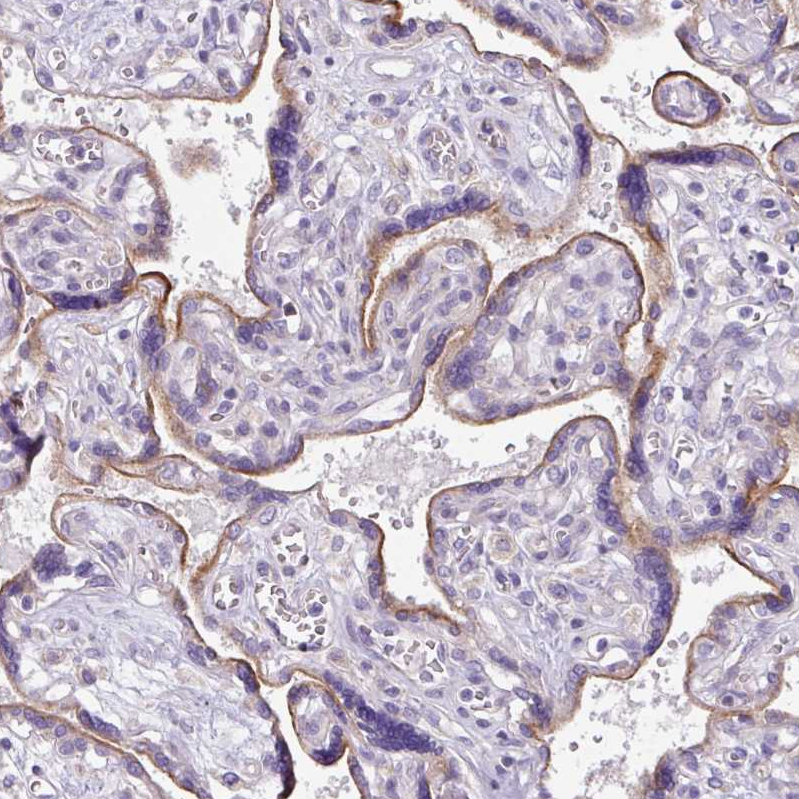

Immunohistochemical staining of human kidney shows strong membranous positivity in cells in tubules.